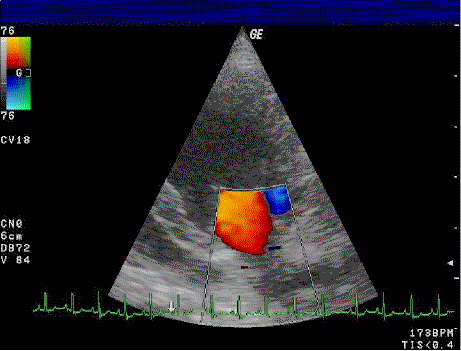

L'échocardiographie ou échographie cardiaque ou écho-doppler cardiaque est une échographie du cœur. Il s'agit d'une technique d' employant les ultrasons. L'échocardiographie a rapidement trouvé sa place parmi les applications médicales des ultrasons. Elle est de manière courante couplée à un examen doppler : on parle alors déchographie-doppler cardiaque. L’échocardiogramme correspond aux images réalisées. L’échocardiographe est l'appareil permettant de réaliser une échocardiographie. Le cœur est un organe intra thoracique, entouré d'air (les poumons) et d'os (les côtes). Ces deux dernières structures ne laissent pas transmettre les ultrasons, rendant l'examen plus complexe. On se sert ainsi d'un nombre limité de « fenêtres » anatomiques, lieux où le cœur peut être visualisé par l'échocardiographie, sans interposition aérienne ou osseuse. Le cœur est un organe tridimensionnel mobile. La prise en compte de cette quatrième dimension (le temps) est nécessaire pour une bonne appréhension de l'organe dans sa globalité. Cela nécessite une résolution temporelle suffisante pouvant être caractérisée par la cadence d'acquisition des images : elle doit être au moins d'une vingtaine images/s et idéalement supérieure à 50 images/s (pour permettre une visualisation correcte en ralenti, surtout si la fréquence cardiaque est élevée). De même, l'analyse à l'aide d'une image, par essence, bidimensionnelle, d'un organe quadridimensionnel, impose certains artifices : c'est le mode Tm (pour l' time motion), utilisé de manière courante, avec en abscisse le déroulement du temps et en ordonnée les échos détectés sur une seule ligne de tir. Le cœur étant mobile, il est important d'évaluer des vitesses. Ces dernières peuvent être calculées en rapportant une distance par rapport au temps (en mode Tm par exemple). Il est cependant plus simple d'employer l'effet Doppler qui déduit de la variation de la fréquence de l'écho réfléchi, la vitesse de l'obstacle responsable de la réflexion. En échocardiographie on peut analyser la vitesse : du sang (en fait celui des hématies ou globules rouges).